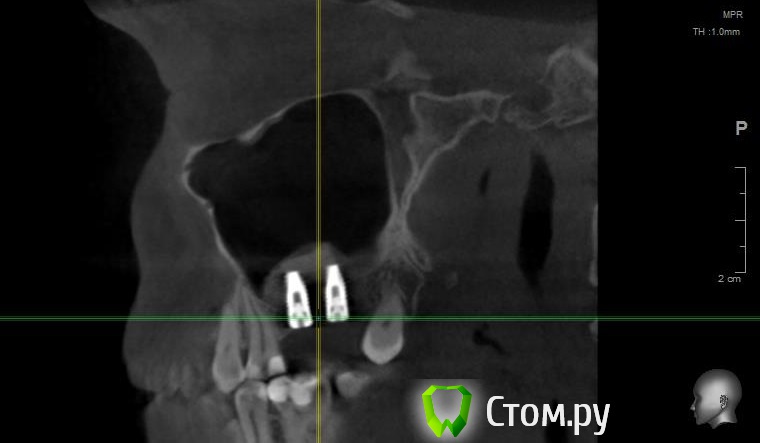

Майло Опубликовано 18 марта, 2014 Автор Поделиться Опубликовано 18 марта, 2014 (изменено) Здравствуйте, наконец сделала кт. Сегодня появилась небольшая боль над правой бровью (после лазера прошла, к вечеру появилась опять). Насморк и заложенность присутствуют. Еще сегодня опять поговорила со своим хирургом имплантологом. По симптомам сказал, что похоже присоединилась какая-то лор болячка и наверное надо сходить к лору. По кт сказал, что все нормально. Немного сужена пазуха справа, но учитывая, что я аллергичная, это нормально. Про капли типа Полидекса, сказал спросить у лора. Завтра я делаю последний лазер, по прежнему промываю нос Отривином Бэби (мне так удобней), пью кларитин, "выбиваю" нос по необходимости, но стараюсь пореже (2-3 раза в день). Еще он отдал кт через 2 недели после имплантации, на всякий случай прикреплю и этот снимок. Самый первый снимок кт был сделан через 2 недели после имплантации. Второй и третий сегодня. Подскажите, я так понимаю данное кт не показывает есть ли у меня гайморит? (к лору смогла записаться аж на 26-е) И все равно хотелось бы узнать ваше мнение по поводу состояния имплантов, есть ли там воспаление или "нагноение"? Изменено 18 марта, 2014 пользователем Майло Ссылка на комментарий

Майло Опубликовано 18 марта, 2014 Автор Поделиться Опубликовано 18 марта, 2014 (изменено) Решила еще добавить пару кадров своих пазух, вначале показалось что справа что-то есть (рис1), потом поняла это костный материал и импланты (рис2). Надеюсь так должно быть. И еще вопрос, может и "тупой", такое яркое свечение имплантов, особенно заметно на фото в профиль, это нормально? Изменено 18 марта, 2014 пользователем Майло Ссылка на комментарий

Bier Опубликовано 18 марта, 2014 Поделиться Опубликовано 18 марта, 2014 выглядит все неплохо, и пазуха чистая. Гайморита у вас нет. Сходите к ЛОРУ 2 Ссылка на комментарий

Майло Опубликовано 19 марта, 2014 Автор Поделиться Опубликовано 19 марта, 2014 (изменено) выглядит все неплохо, и пазуха чистая. Гайморита у вас нет. Сходите к ЛОРУСпасибо. А такие затемнения вокруг имплатов, это нормально? Изменено 19 марта, 2014 пользователем Майло Ссылка на комментарий

red_butler Опубликовано 19 марта, 2014 Поделиться Опубликовано 19 марта, 2014 Да, это артефакты вызванные металлом Ссылка на комментарий